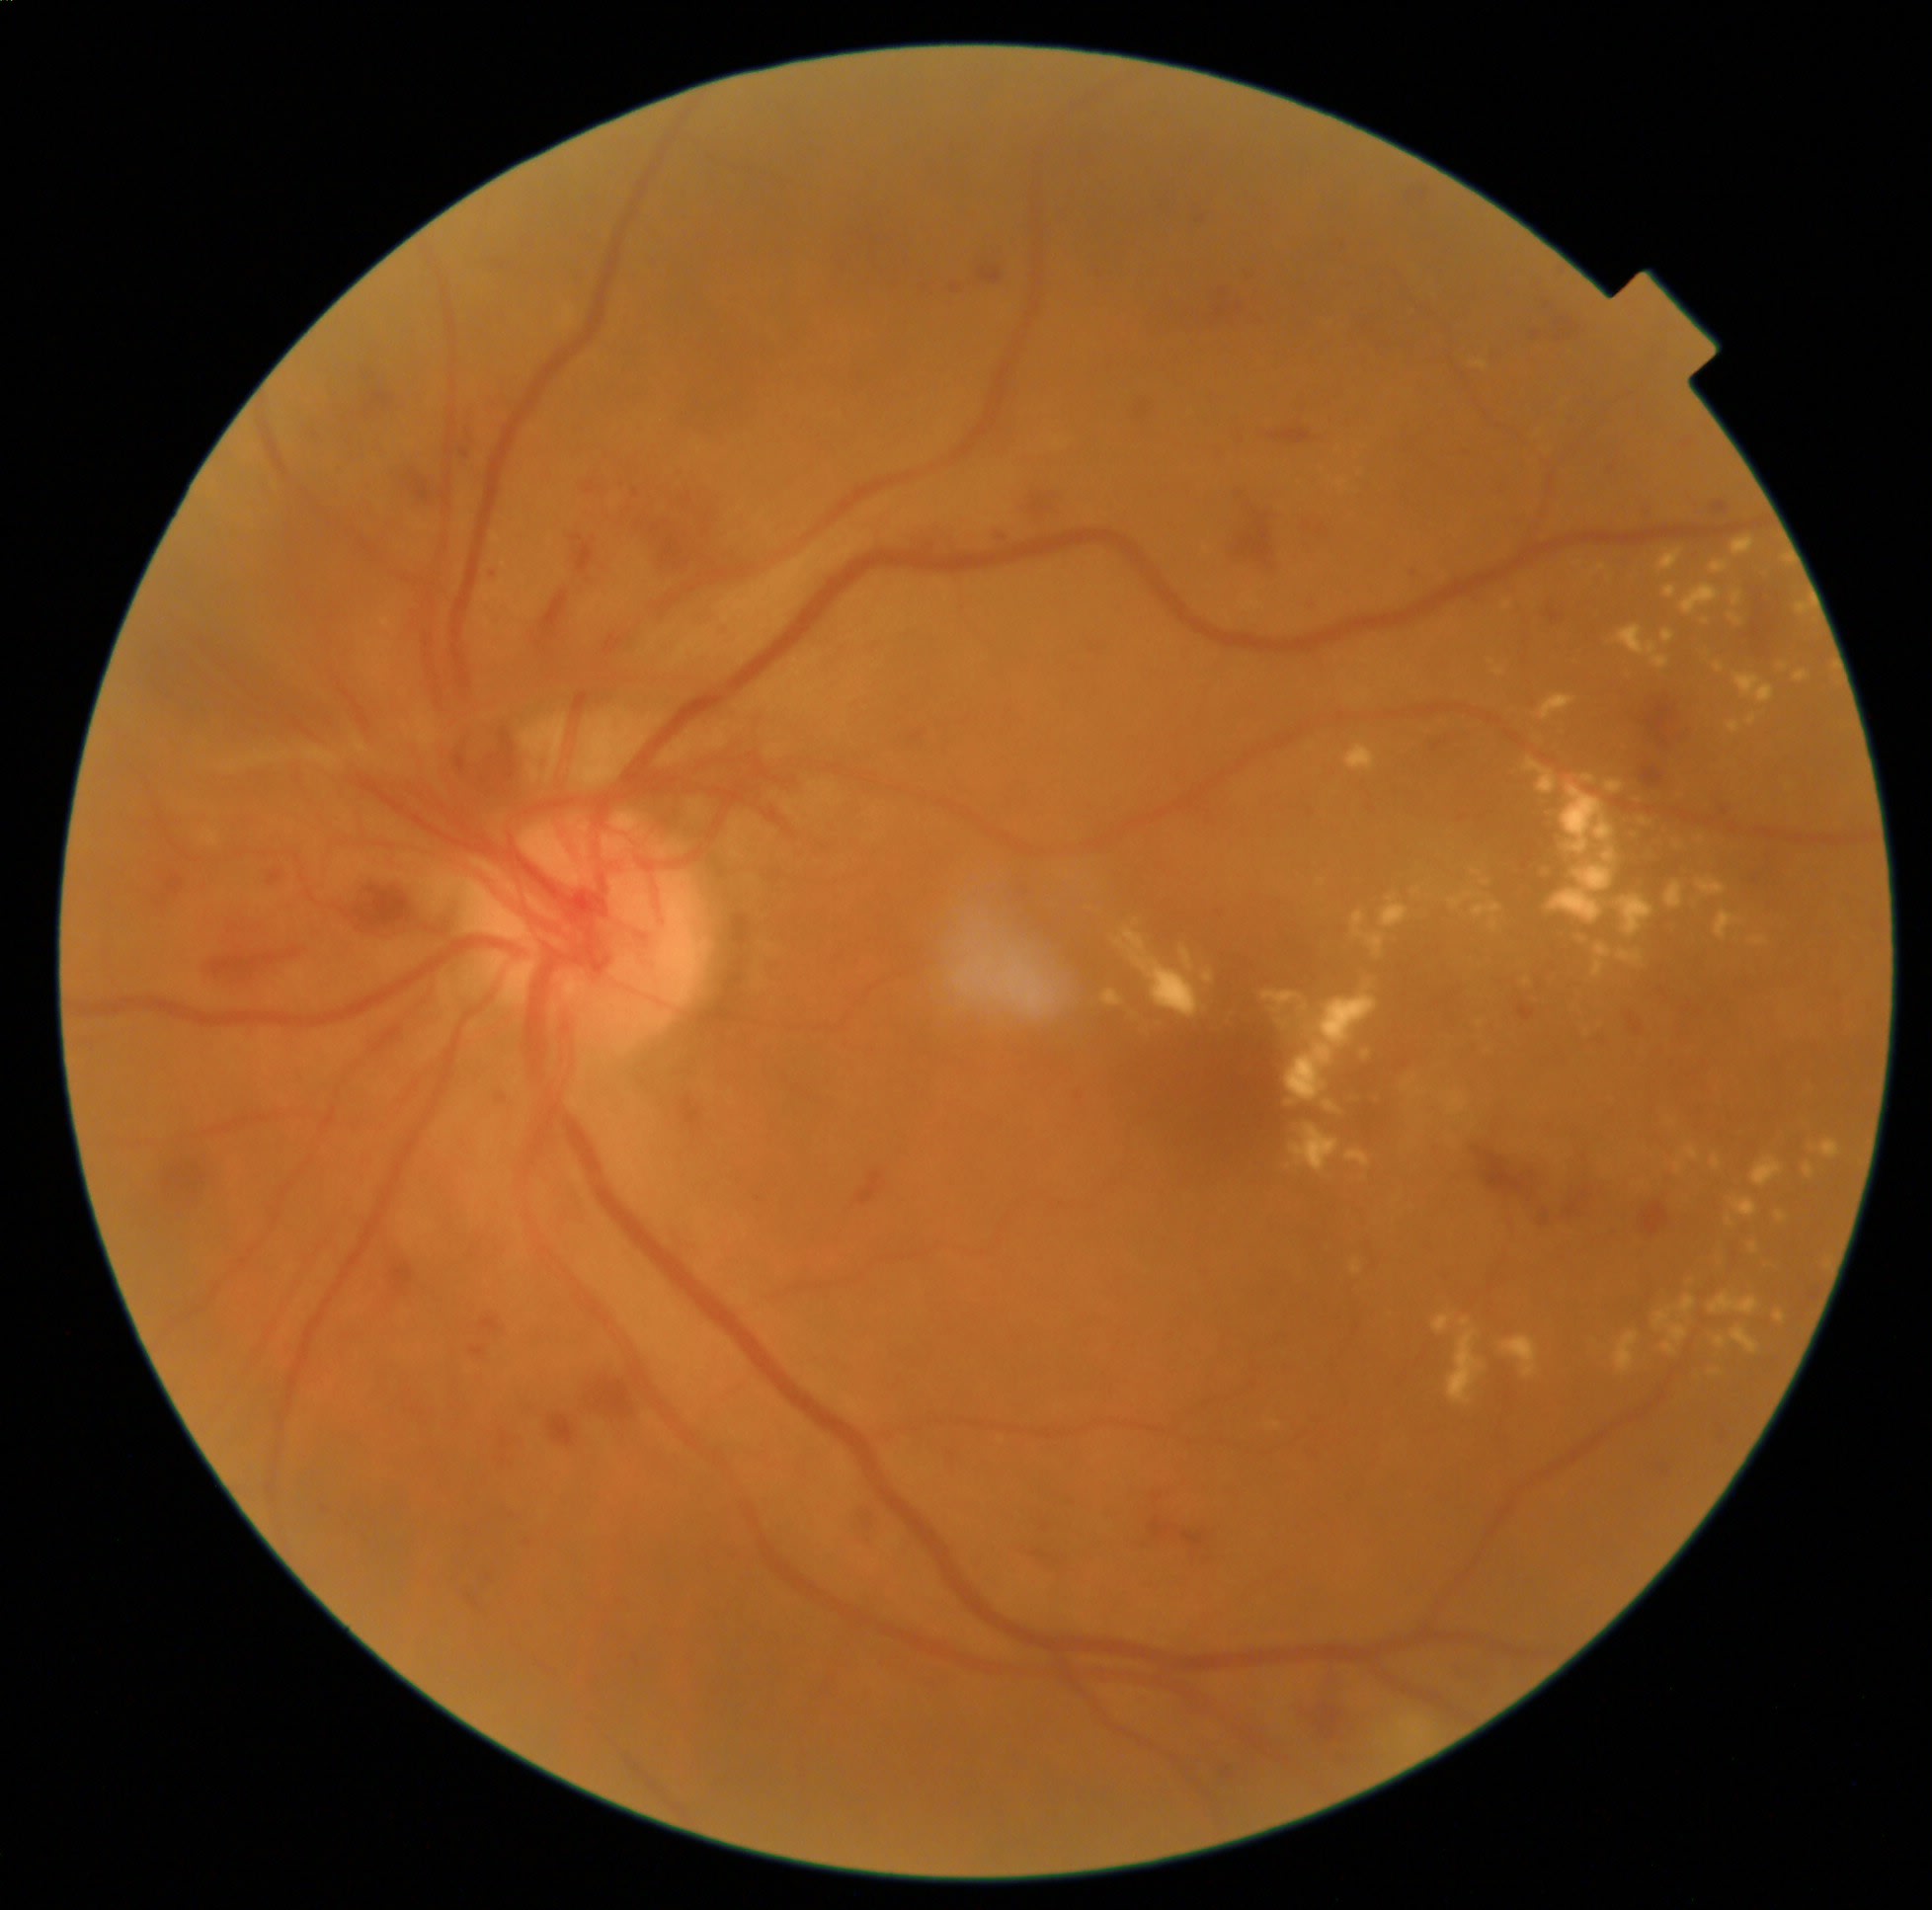

Focal or grid photocoagulation: I’ve identified a small red dot with surrounding leakage within your macula, the area that supplies your central vision. This leak can threaten your vision if left untreated. A method of focal laser targeting a single focal point can help seal the area of leaking. If the leakage is more widespread and a point of leak is difficult to discern, a grid pattern laser can be applied to help stop the leaking of fluid. This helps prevent further swelling in the center part of your retina and aids in reducing existing swelling.

Panretinal photocoagulation: In advanced stages of diabetic retinopathy, abnormal blood vessels can develop in the back of the eye due to areas of the retina that are deprived of oxygen. These vessels are prone to leakage, which can lead to vision-threatening complications. A procedure called panretinal photocoagulation employs a laser to create small burns within the retina that is deprived of oxygen and causing the proliferation of the abnormal blood vessels. Panretinal photocoagulation, which can be performed multiple times, is shown to reduce the risk of severe vision loss by 50%.7

Educating patients about the purpose of these treatments and what they can expect both during and after treatment allows them time to reflect, research, and ultimately make an informed decision about their ocular health. It’s no secret, that much of verbal communication can be forgotten by patients, so I recommend providing patients with supporting documentation of these scripts and, possibly using imaging of their DR to make a lasting impression. Finally, in recognizing time is at a premium for optometrists, I suggest considering having an allied staff member present when providing this education, so they can repeat it to patients and answer any questions.